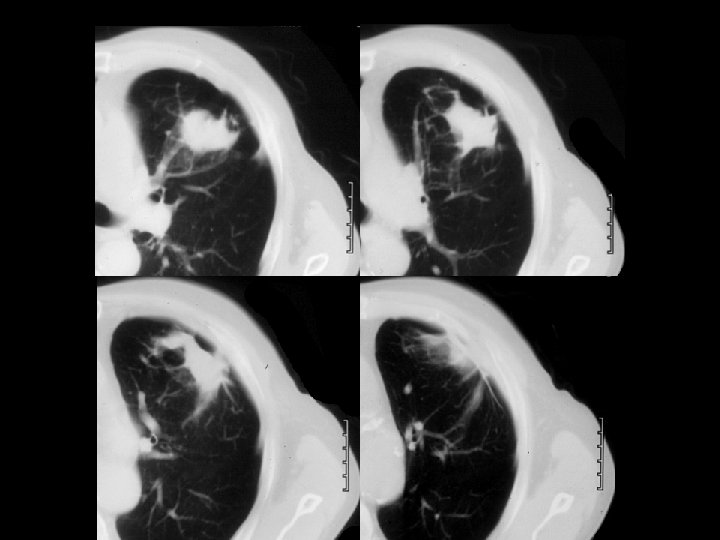

Findings and Differentials Findings: Frontal and lateral chest radiographs demonstrate a 3 -4 centimeter left upper lobe mass with surrounding areas of hyperlucency and arcuate parenchymal distortion. A healed left upper posterior rib fracture is noted. Four CT images show the irregular left upper lobe mass with peripheral attachment to thickened pleura. Note the parenchymal distortion in association with the inferomedial aspect of the lesion. Differentials: • Round atelectasis • Primary bronchogenic carcinoma

Discussion Round atelectasis (also known as rounded atelectasis) is a form of pseudotumor that often mimics a bronchogenic carcinoma. It is most often associated with prior asbestos exposure but can be caused by other insults including trauma. In theory, any process that results in development of a pleural effusion with associated atelectasis can result in round atelectasis. Specifically, if an effusion results in fibrinous adhesions to the atelectatic lung, subsequent lung trapping results in a “rolling up” of this portion of lung. As the effusion clears, the remaining lung in the region re-expands, leaving only the “rolled up”, trapped lung as evidence of prior effusion. Thus, round atelectasis is a peripheral process requiring adhesions with the pleura. As noted in the initial chest radiograph and associated CT images in this case, The arcuate parenchymal distortion in association with the mass represents bronchovascular structures trapped in the “rolled up” atelectatic lung. The inferomedial location of this parenchymal distortion with respect to the hilus of the mass has been termed the comet tail sign. Of the four choices given in the initial diagnosis section, the most likely options are round atelectasis and bronchogenic carcinoma. Round pneumonia is not common in adults, and the mass appearance is overall less typical for metastasis.